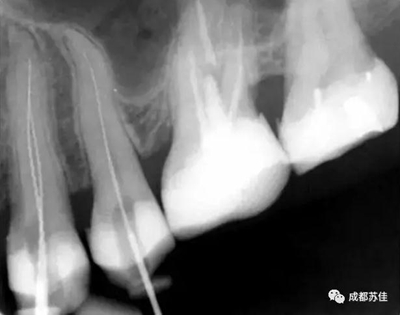

空間分辨率最高可達16.7lp/mm,16位(65,636)的灰度,能夠可靠的分辨出D1級別的齲損及細小至ISO 06 級別的根管器械。